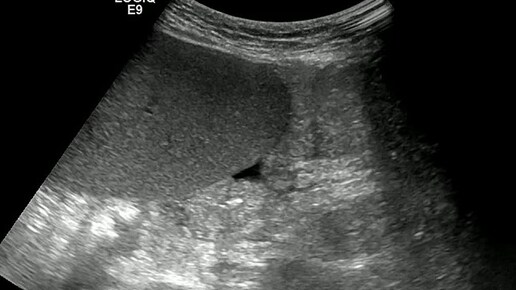

Видео к статье: "Свободная жидкость в брюшной полости"https://dzen.ru/a/Z-1KdOK-KyrjRiGF

Ультразвуковые находки от врача УЗД Зорина Я.П.